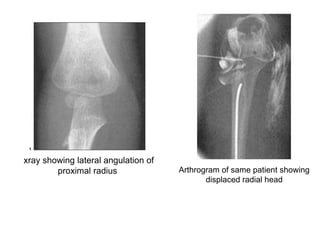

• The diagnosis of a partially or completely displaced

fracture of the radial neck may be difficult in

children whose radial head remains unossified.88

• The only clue may be a little irregularity in the

smoothness of the proximal metaphyseal

margin.

• Displacement of supinator fat or anterior/posterior

humeral fat pad may indicate fracture but not

always.

• MRI is best in these cases.

• Arthrogram, ultrasound, or MRI are helpful to

assess the extent of the displacement and the

accuracy of reduction in children with an unossified

radial epiphysis.

• In the preossification stage, on the AP radiograph, the edge of the metaphysis of

the proximal radius slopes distally on its lateral border.

• This angulation is normal and not a fracture.

• In the AP view, the lateral angulation varies from 0 to 15 degrees, with the average

being 12.5 degrees.

• In the lateral view, the angulation can vary from 10 degrees anterior to 5 degrees

posterior, with the average being 3.5 degrees anterior .

xray showing lateral angulation of

proximal radius Arthrogram of same patient showing

displaced radial head